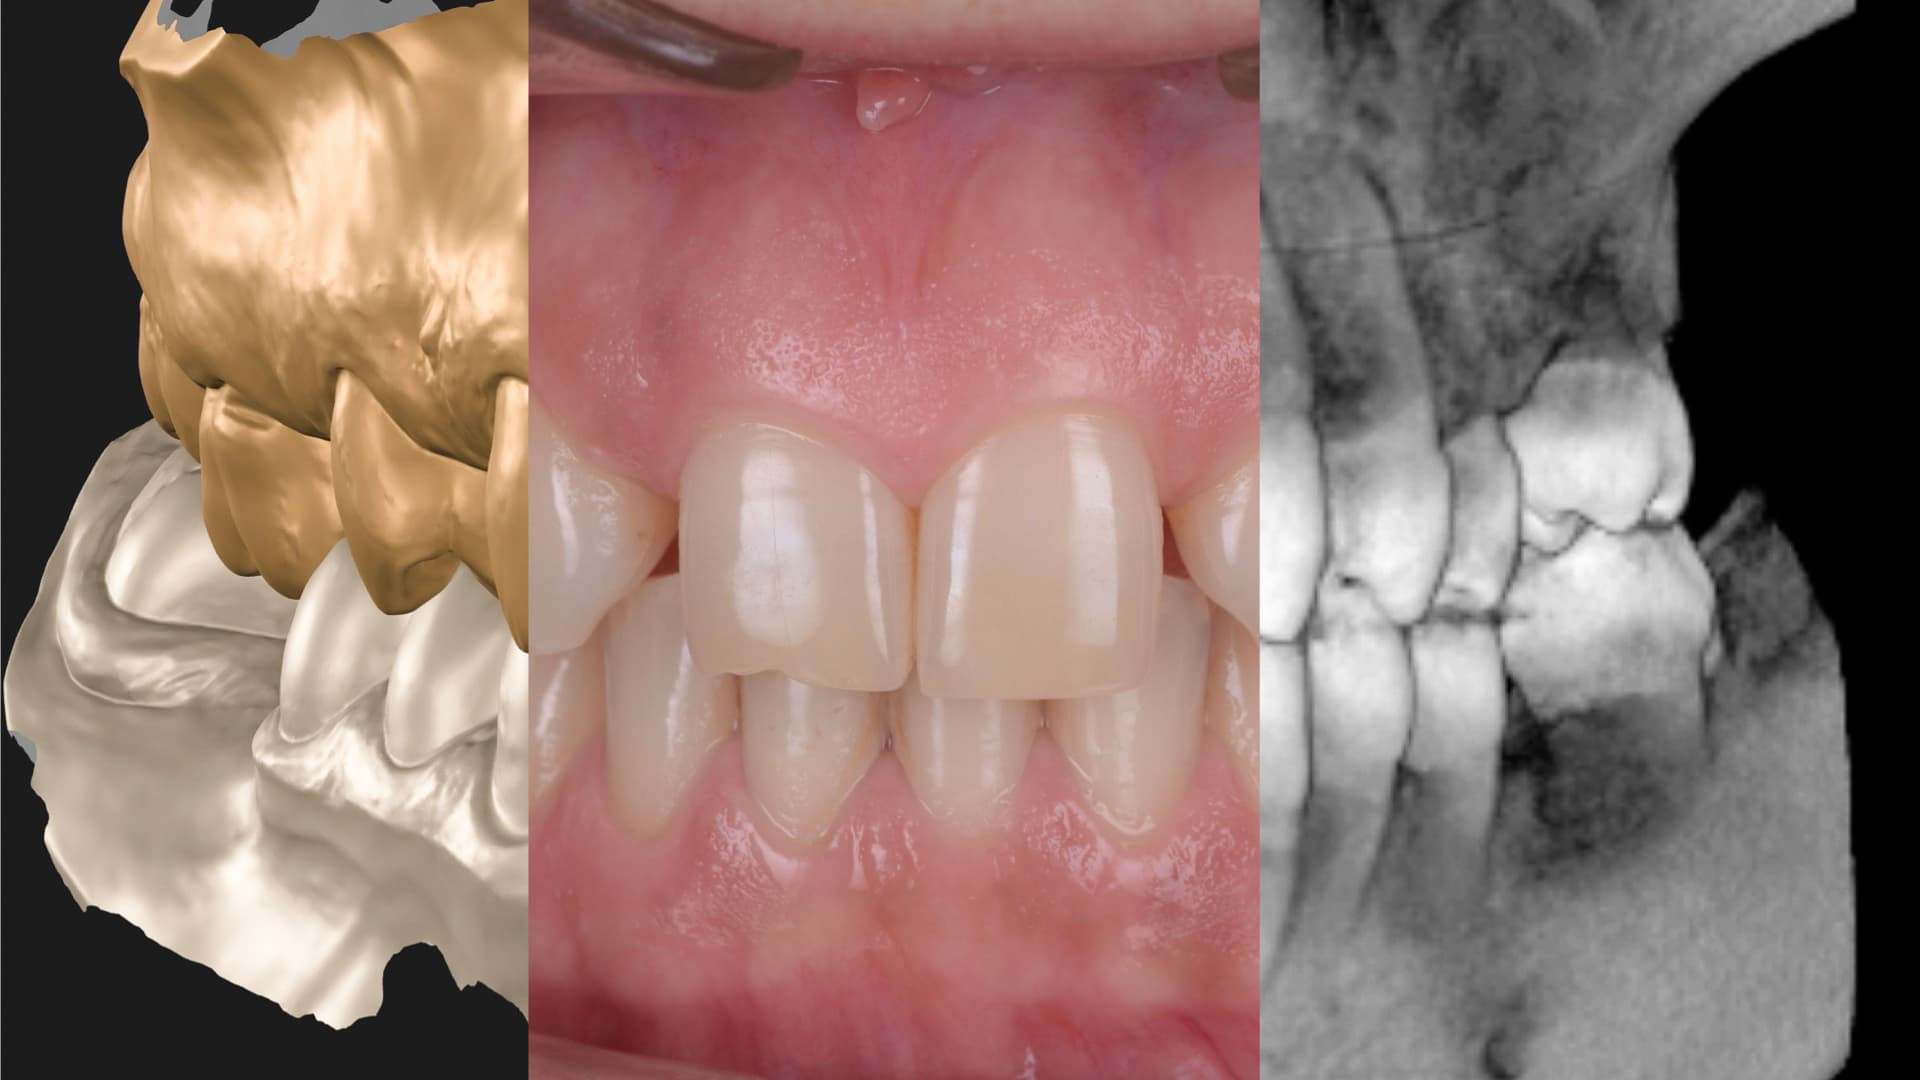

Every aligner case begins with a facially guided digital plan. Using 3D scans, bite analysis, and photos, we simulate the ideal outcome before moving a single tooth. This ensures that every shift supports not only alignment, but also future restorative needs, gum levels, and bite stability.

Fully Digital Workflow

Our aligner workflows are fully digital, which means greater comfort, accuracy, and efficiency. Everything is stored and reproducible, giving you long-term flexibility.

Before treatment begins, you preview the final result. Our mock-ups and simulations let you understand the full plan—visually and functionally—so you can make an informed decision.